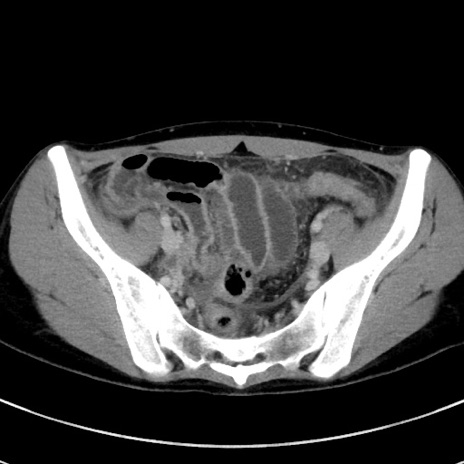

冠状断像

【症例】20歳代女性

【主訴】嘔吐、下腹部痛

【現病歴】昨日夕食後に嘔吐し下腹部痛が出現。本日になっても嘔吐持続し改善しないため来院。

【身体所見】意識清明、BT 37.2℃、BP 108/67mmHg、腹部:平坦、やや硬、下腹部正中から右にかけて圧痛あり、反跳痛軽度あり、tapping pain(+)。

【データ】WBC 13600、CRP 14.94